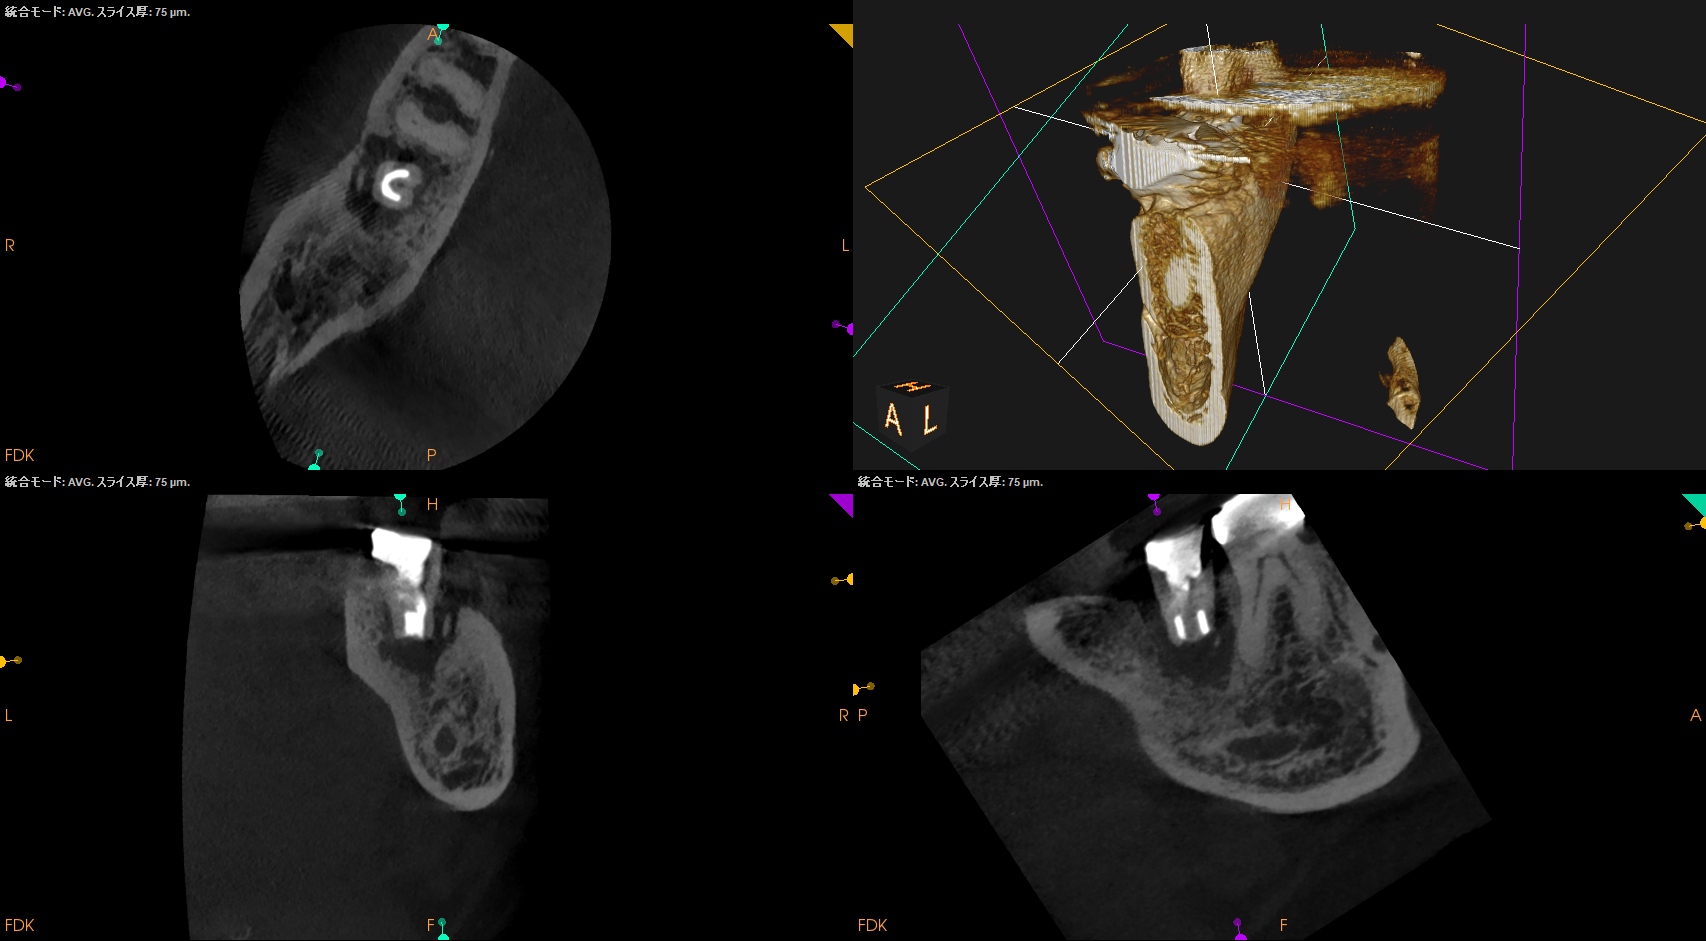

#31 Intentional Replantation 6M recall(2025.11.20)

歯牙の動揺も、

頬側の歯周ポケットも消失した。

術前の臨床症状もない。

ML

MB

D

初診時と比較した。

初診時の絶望的な状況から改善されている。

最終補綴もOKと言えるだろう。

結論を言えばこの歯周ポケットはエンドが作ったものだったのだろう。

が、エンド病変が治癒したらそれが改善されている。

エンド→ペリオ病変であったと言うことだ。